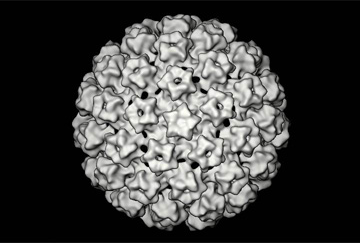

Il vaccino contro l’hpv viene offerto gratuitamente a tutte le bambine italiane nel dodicesimo anno di vita a partire dal 2007/2008. Alcune Regioni hanno esteso l’offerta anche alle ragazze di altre fasce di età, mentre la Regione Emilia-Romagna offre i vaccini anche alle persone sieropositive, e nel 2014 Veneto e Puglia hanno esteso l’offerta gratuita ai maschi nel dodicesimo anno di vita.